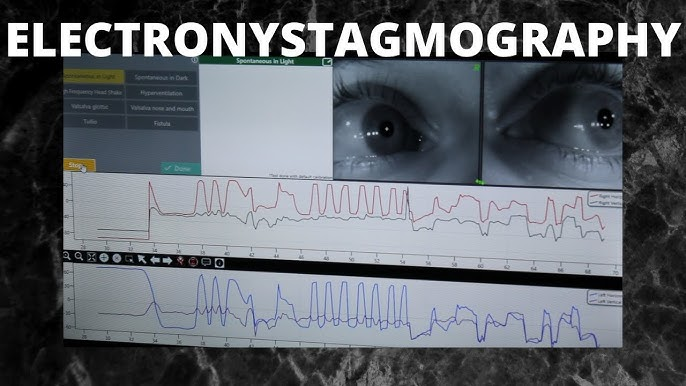

♦Electronystagmography (ઇલેક્ટ્રનેસ્ટેગ્મોગ્રાફી):

An electronystagmography (ENG) test measures your eye movements and the health of your cranial nerves. It involves placing small metal discs (electrodes) around your eyes, which measure nerve function. ENG test to check for balance disorders or other inner ear problems.

- ઇલેક્ટ્રોન।ઈસ્ટીગ્મોગ્રાફી એ સ્પોન્ટેનિયસ ,પોઝીશનલ, આંખની હિલચાલ દ્વારા સર્જાયેલી વિદ્યુત સંભવિતતામાં ફેરફારોનું માપન અને ગ્રાફિક રેકોર્ડ છે.

- એ એક અભ્યાસ છે જેનો ઉપયોગ Dizziness અથવા અસંતુલનની તકલીફ ધરાવતા Medical evaluation of patient કરવા માટે થાય છે.

- આ ટેસ્ટનો ઉપયોગ એ નક્કી કરવા માટે થાય છે વેસ્ટિબ્યુલર સિસ્ટમ કેજે ratina ને સ્થિર કરવા માટે માથાની સ્થિતિ અને હલનચલન નું નિરીક્ષણ કરે છે.

- આ માહિતી vestibulocochlear રિફ્લેક્સ ઉત્પન્ન કરવા માટે બ્રેન stems માં દ્રશ્ય વિજ્યુઅલ અને spine ના સબંધ સાથે સંકલિત છે.